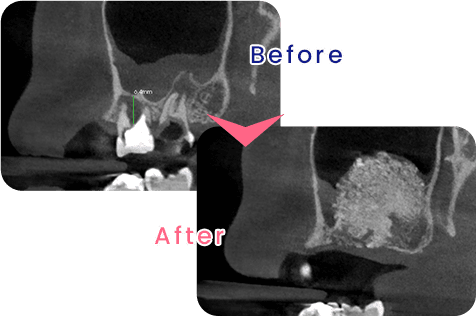

GBR(骨誘導再生法)と呼ばれる手術方法です。インプラントを顎の骨に埋め込む際、十分な骨の高さや厚みが必要になりますが、歯周病や加齢により顎の骨が不足している自家骨(自分の骨)や、人工的な材料を使用し、数ヶ月間の治療機関を経て骨が再生します。

当院のインプラント治療